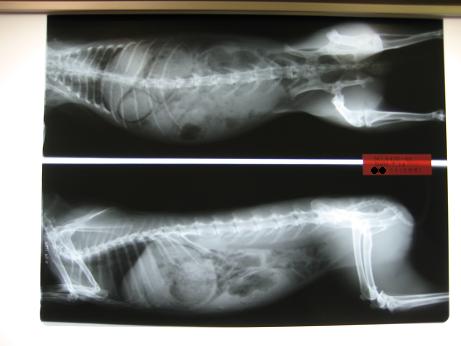

まり『お腹が張ってる気もするし、久々にレントゲンも

撮ってもらおっか

先生がうりのレントゲン、問題ない。って

まり『でも実際、200gぐらい体重も減ってるし、

換毛期で毛が溜まってるから食が細くなってるかも

しれんしなぁ。レントゲンには毛は写らないみたい

だし、お薬だけもらって帰ろな